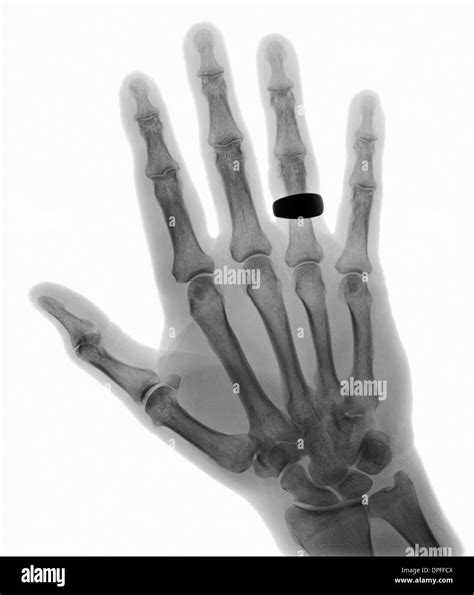

💡 Note: Remove all jewelry, such as rings or watches, from the hand and wrist area before the procedure to prevent artifacts from appearing on the final image.

• Soft Tissue Shadows: While X-rays are primarily for bones, a skilled professional also checks the surrounding soft tissues for swelling or shadows that could suggest a hidden injury or foreign body.